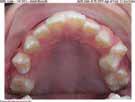

LOVE YOUR SMILE!

Mahaffey Linkous Orthodontics offers braces and lnvisalign® in conjunction with modern techniques to conveniently uncover your best smile. Dr. Michael Mahaffey, Dr. Eric Linkous, and their caring team of tooth-moving experts make having orthodontic treatment an awesome experience! Schedule your complimentary consultation today to begin your journey to a healthier, more confident smile.